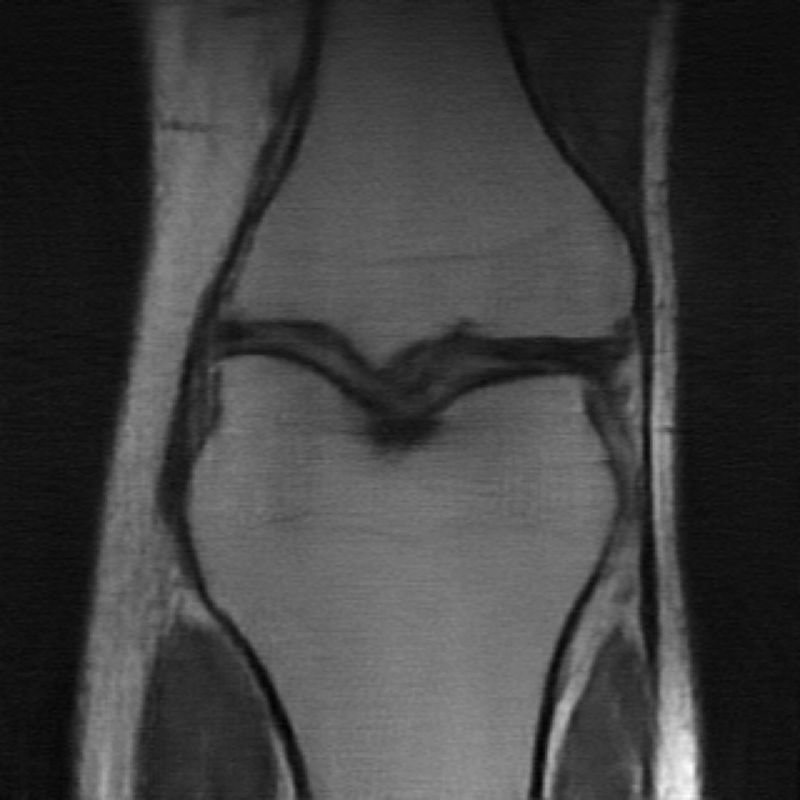

MRI reconstruction is performed with a undersampling of k-space in the phase encoding direction for both and . The sampling maps are shown in Fig 4.

| (a) Original k-space sampling pattern () | (b) Resampled k-space sampling pattern () |

The data used in the undersampled MRI experiments were obtained from the NYU fastMRI Initiative [45]. The primary goal of the fastMRI dataset is to test whether machine learning can aid in the reconstruction of medical images. We trained and tested on a subset of the single-coil knee dataset, which consist of simulated single-coil measurements. In all tests, we use complex-valued data, which interfaces with our deep networks by treating the real and imaginary parts of the images as separate channels. We measure reconstruction accuracy with respect to the center 320320 pixels of the complex IFFT of the fully-sampled k-space data. For the purpose of visualization, we display only the magnitude images in the following sections.

In the case of MRI, we use two choices of , depending on whether we assume is fully known or not. In the case is fully known, we utilize another undersampled k-space mask, but with resampled high-frequency lines. We display the original and new k-space sampling masks in Figure 4. To illustrate the utility of our approach under miscalibration of the forward model in an MRI reconstruction setting, we also consider a unknown random perturbation of the original k-space lines, which we attempt to learn during reconstruction. The vertical k-space lines are still fully sampled, as are the center 4 of frequencies, but all high frequency lines are perturbed uniformly at random with a continuous value from -2 to 2. We wish to emphasize that this experiment is not meant to reflect clinical practice, since such miscalibration of k-space sampling locations is not typically encountered in anatomical imaging with Cartesian k-space sampling trajectories. However, we include this experiment simply to illustrate that our approach could be extended to unknown parametric changes in the forward model in an MR reconstruction setting.